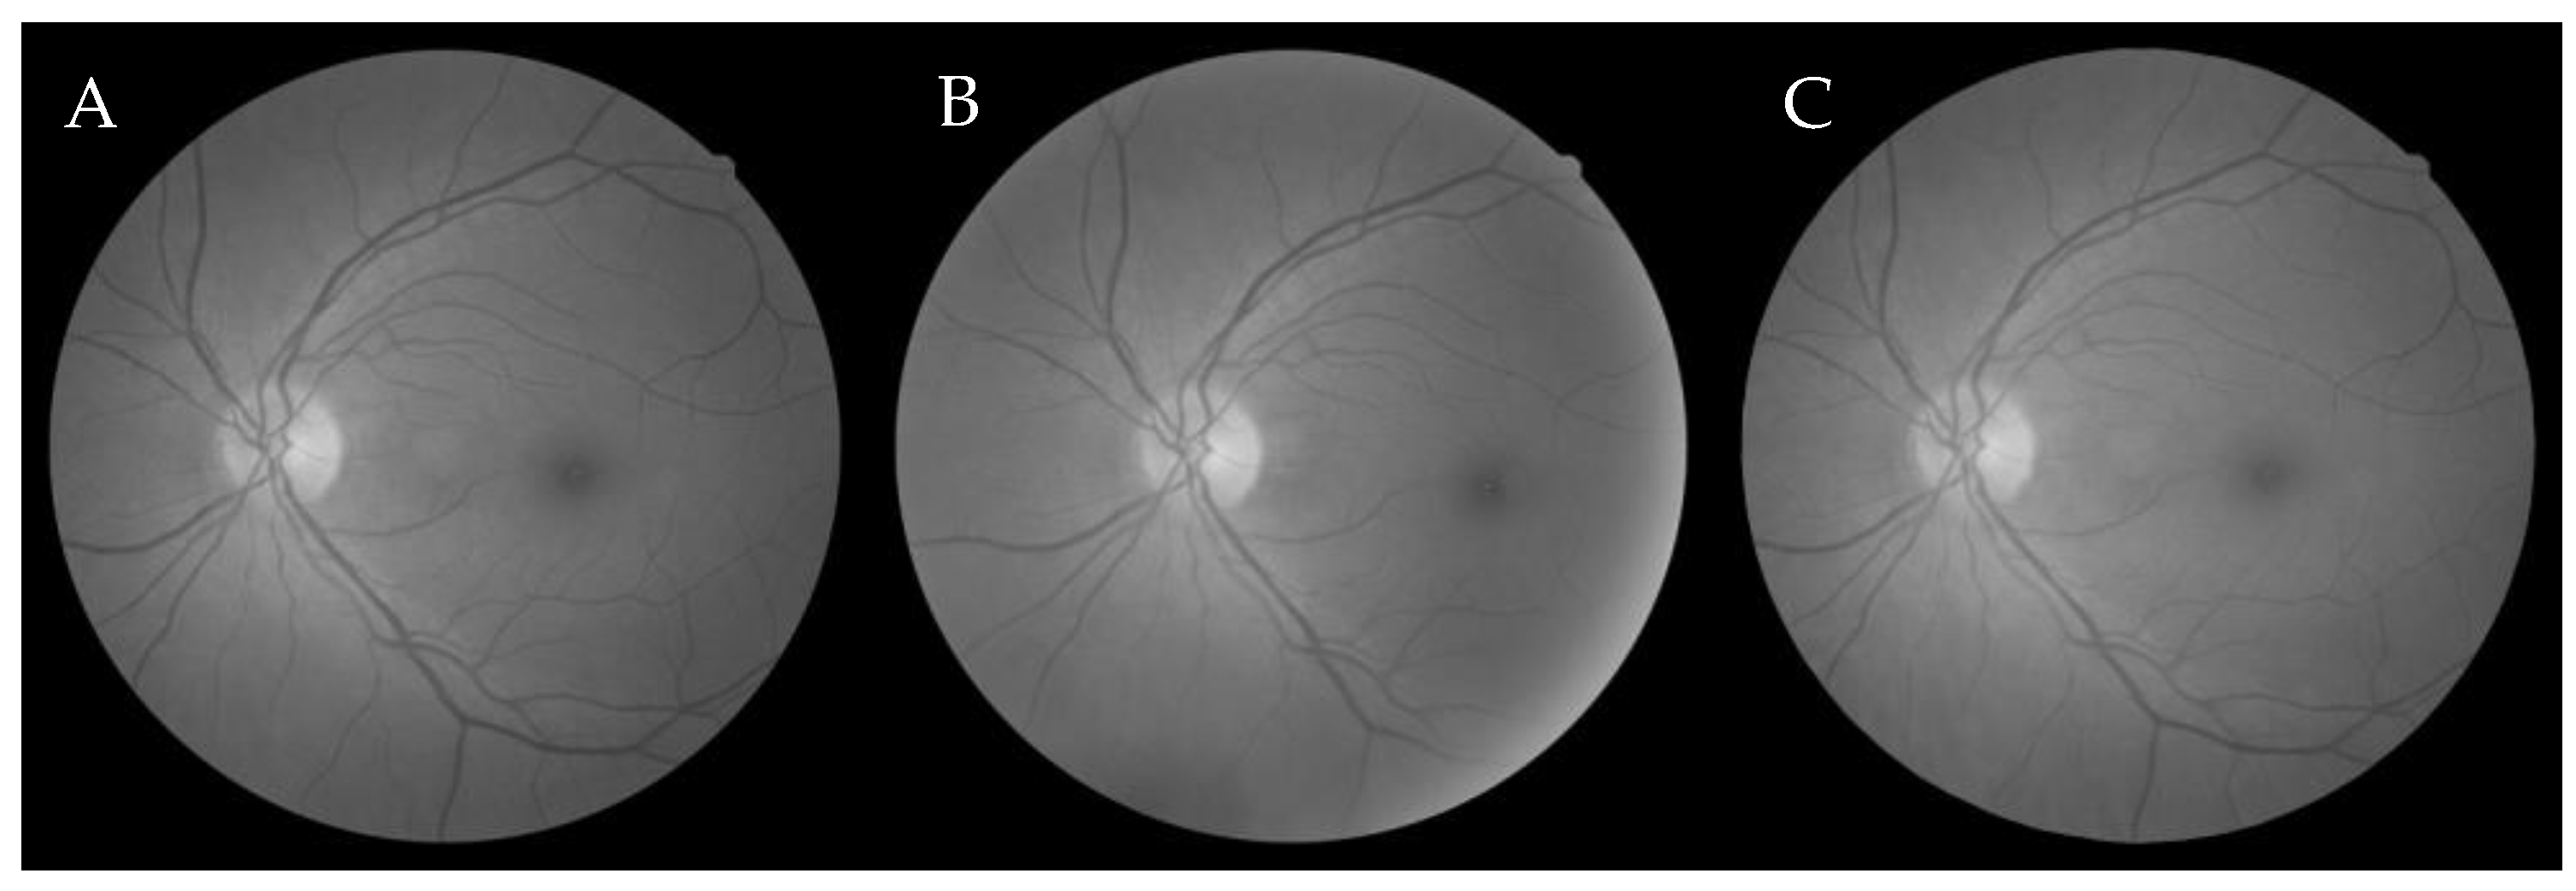

6.1. Dataset

6.2.1. Grey-Wolf Optimization-Based Wang’s Demons Registration